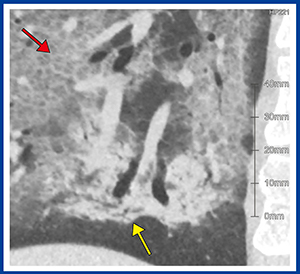

「QZIP-ILD」は,COVID-19肺炎への応用も可能である。症例2は,30歳代,男性,肺の両側にGGOが見られ,典型的なCOVID-19肺炎である。本症例はHRCTで撮影し,1024×1024マトリックス,0.25mmスライス厚で画像再構成を行った。現在,1024マトリックスのHRCTの画像を観察できるワークステーションは限られているが,同社の「Ziostation2」ではこれらの画像データに対応し,MPRでの観察も容易である。病変部を拡大(図3)すると,コンソリデーション内部に,呼吸細気管支と思われる細かい分岐状の気腔(↑)が認められるほか,crazy paving pattern内部では正常肺と比較して小葉が小さいことも確認できる(↓)。「QZIP-ILD」による定量解析結果を見ると,本症例では局所の容積低下はあるものの,肺全体の体積は予測全肺気量の100%で低下は見られず(図4),本症例では肺炎は改善した。

図3 1024マトリックスのHRCT

画像に対応した「Ziostation2」による観察

(症例2:COVID-19肺炎)